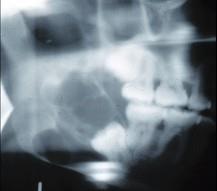

女,32岁,右下后牙龈向外膨隆,后牙渐松动3个月。X线片(如图)示右下颌磨牙区颌骨呈蜂房样改变,病变区牙根呈锯齿状吸收。该病人最可能的诊断是 ( )

A.右下颌骨骨肉瘤B.右下颌骨角化囊肿C.右下颌骨成釉细胞瘤D.右下颌骨骨巨细胞瘤E.右下颌骨中央性颌骨癌

C